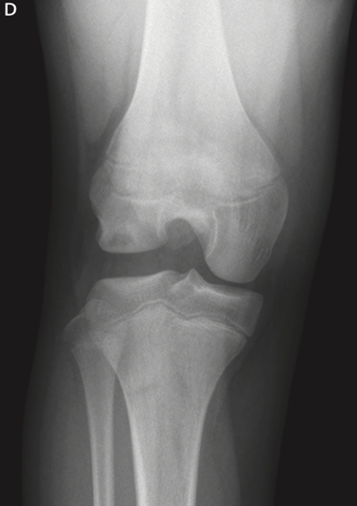

Un esame radiiografico in protezione AP e LL di ginocchio gioca un ruolo importante in primis per la diagnosi differenziale con altre patologie; in secondo luogo, poiché si possono apprezzare dei pattern radiografici tipici come ad esempio: il cosiddetto “Squaring” del condilo femorale laterale (Fig 2), l’ampliamento dell’interlinea femoro-tibia, la concavità del piatto tibiale laterale, l’ipoplasia della spina tibiale laterale, l’incremento dell’altezza della testa del perone.